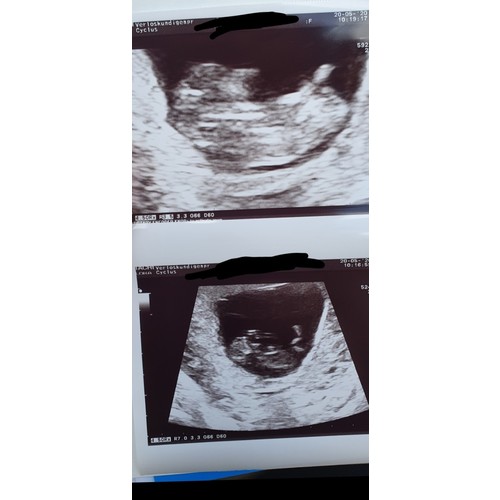

Wilt er iemand mij helpen aub????

Ik kom er echt niet uit 😳 iemand die mij kan helpen?

Twijfelachtig maar ik denk 75% kans dat je meisje krijgt